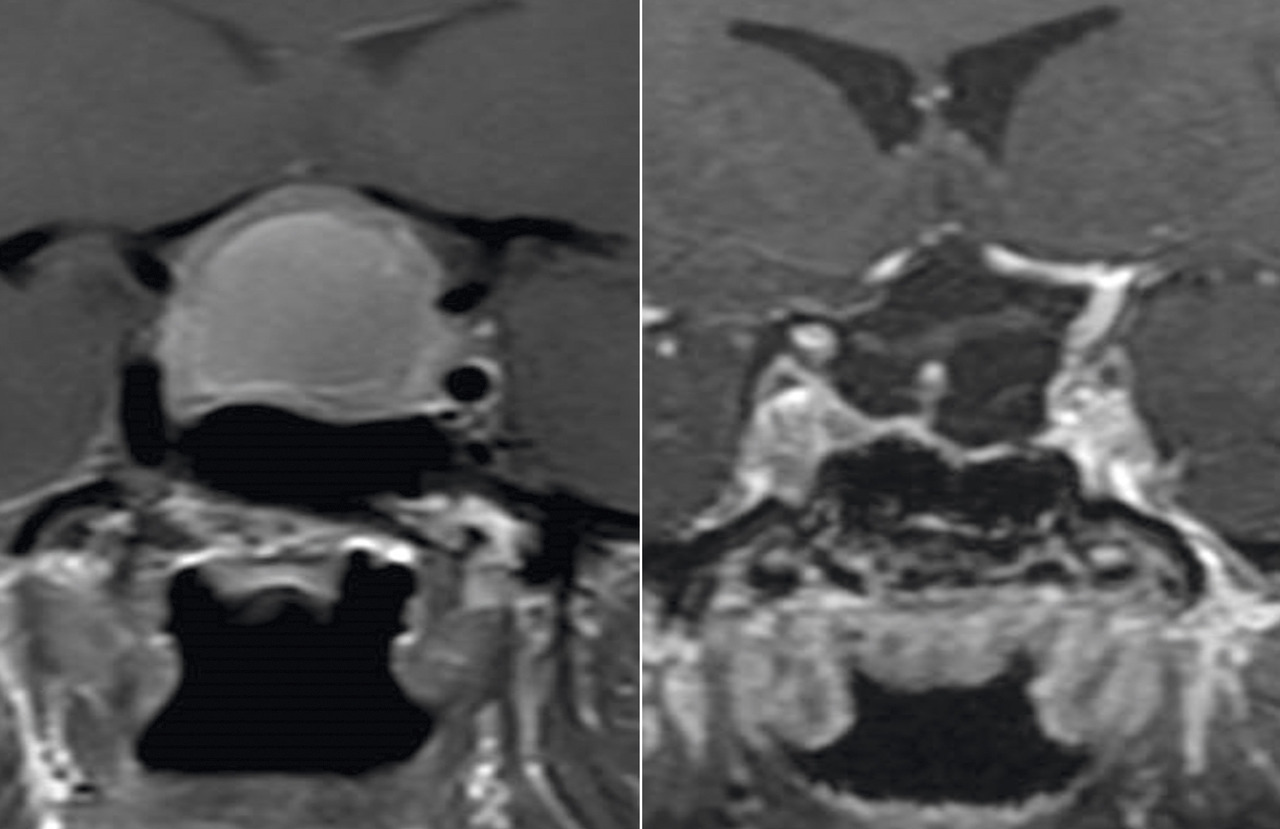

La réalisation d’une IRM centrée sur l’hypophyse est obligatoire devant toute suspicion de diabète insipide à partir des arguments diagnostiques évoqués. Elle permet d’affirmer la présence d’une tumeur de la région hypothalamo-hypophysaire ou de signes d’hypophysite (élargissement de la tige pituitaire notamment) en faveur d’une cause acquise de diabète insipide central.

L’IRM sans lésion peut révéler une perte de signal de la post-hypophyse (signant l’absence de vasopressine), en faveur du diagnostic de diabète insipide idiopathique.

L’adénome hypophysaire, même invasif, n’est classiquement pas pourvoyeur de diabète insipide, à l’exception de situations exceptionnelles de nécrose de l’adénome (apoplexie).